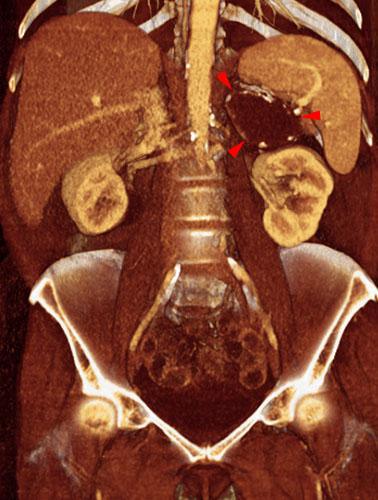

Quiste renal complejo sugestivo de neoplasia